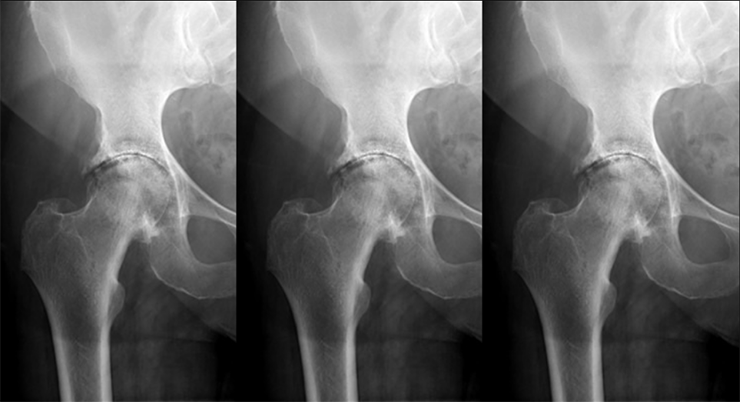

The worn, or sclerotic, bone at the top of the cup is harder to ream than the bone at the bottom.

The patient complained of more pain in the top part of the hip.

The hip bones compensate for excessive wear by growing osteophytes.